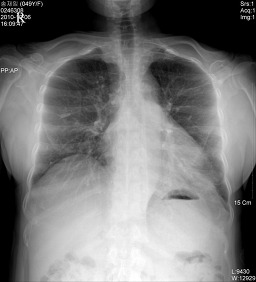

*Chest AP(흉부전후방향촬영법)

검사목적

환자의 상태가 Erect에서는 검사를 할 수 없을 때 시행하며, 폐병소의 검사에 있어서 보충적인 촬영으로도 시행된다.

Central Ray

T-6 높이에 수직으로 입사

Check Point

Apex 부위가 넓게 나왔는가

Clavicle의 농도가 적당하고 hilum의 추구가 가능한가

Scapular가 폐야에서 제거되었는가

Diaphragm의 주행을 추구할 수 있는가

Breast 음영과 hilum을 구분할 수 있는가

Liver 와 lung이 중복된 부분에서 hilum을 구분할 수 있는가

Media Sternum 음영영역이 나타나고 있는가

우심실 2궁과 diaphragm의 교차상이 잘 나타나고 있는가

Clavicle이 대칭으로 잘 나타나고 있는가

Pulsation으로 인한 폐문리의 흐림이 적은가

심장과 폐가 중복되고 있는 부분의 hilum은 잘 구분할 수 있는가

costophrenic angle이 잘 나타나고 있는가

collimation이 적절한가